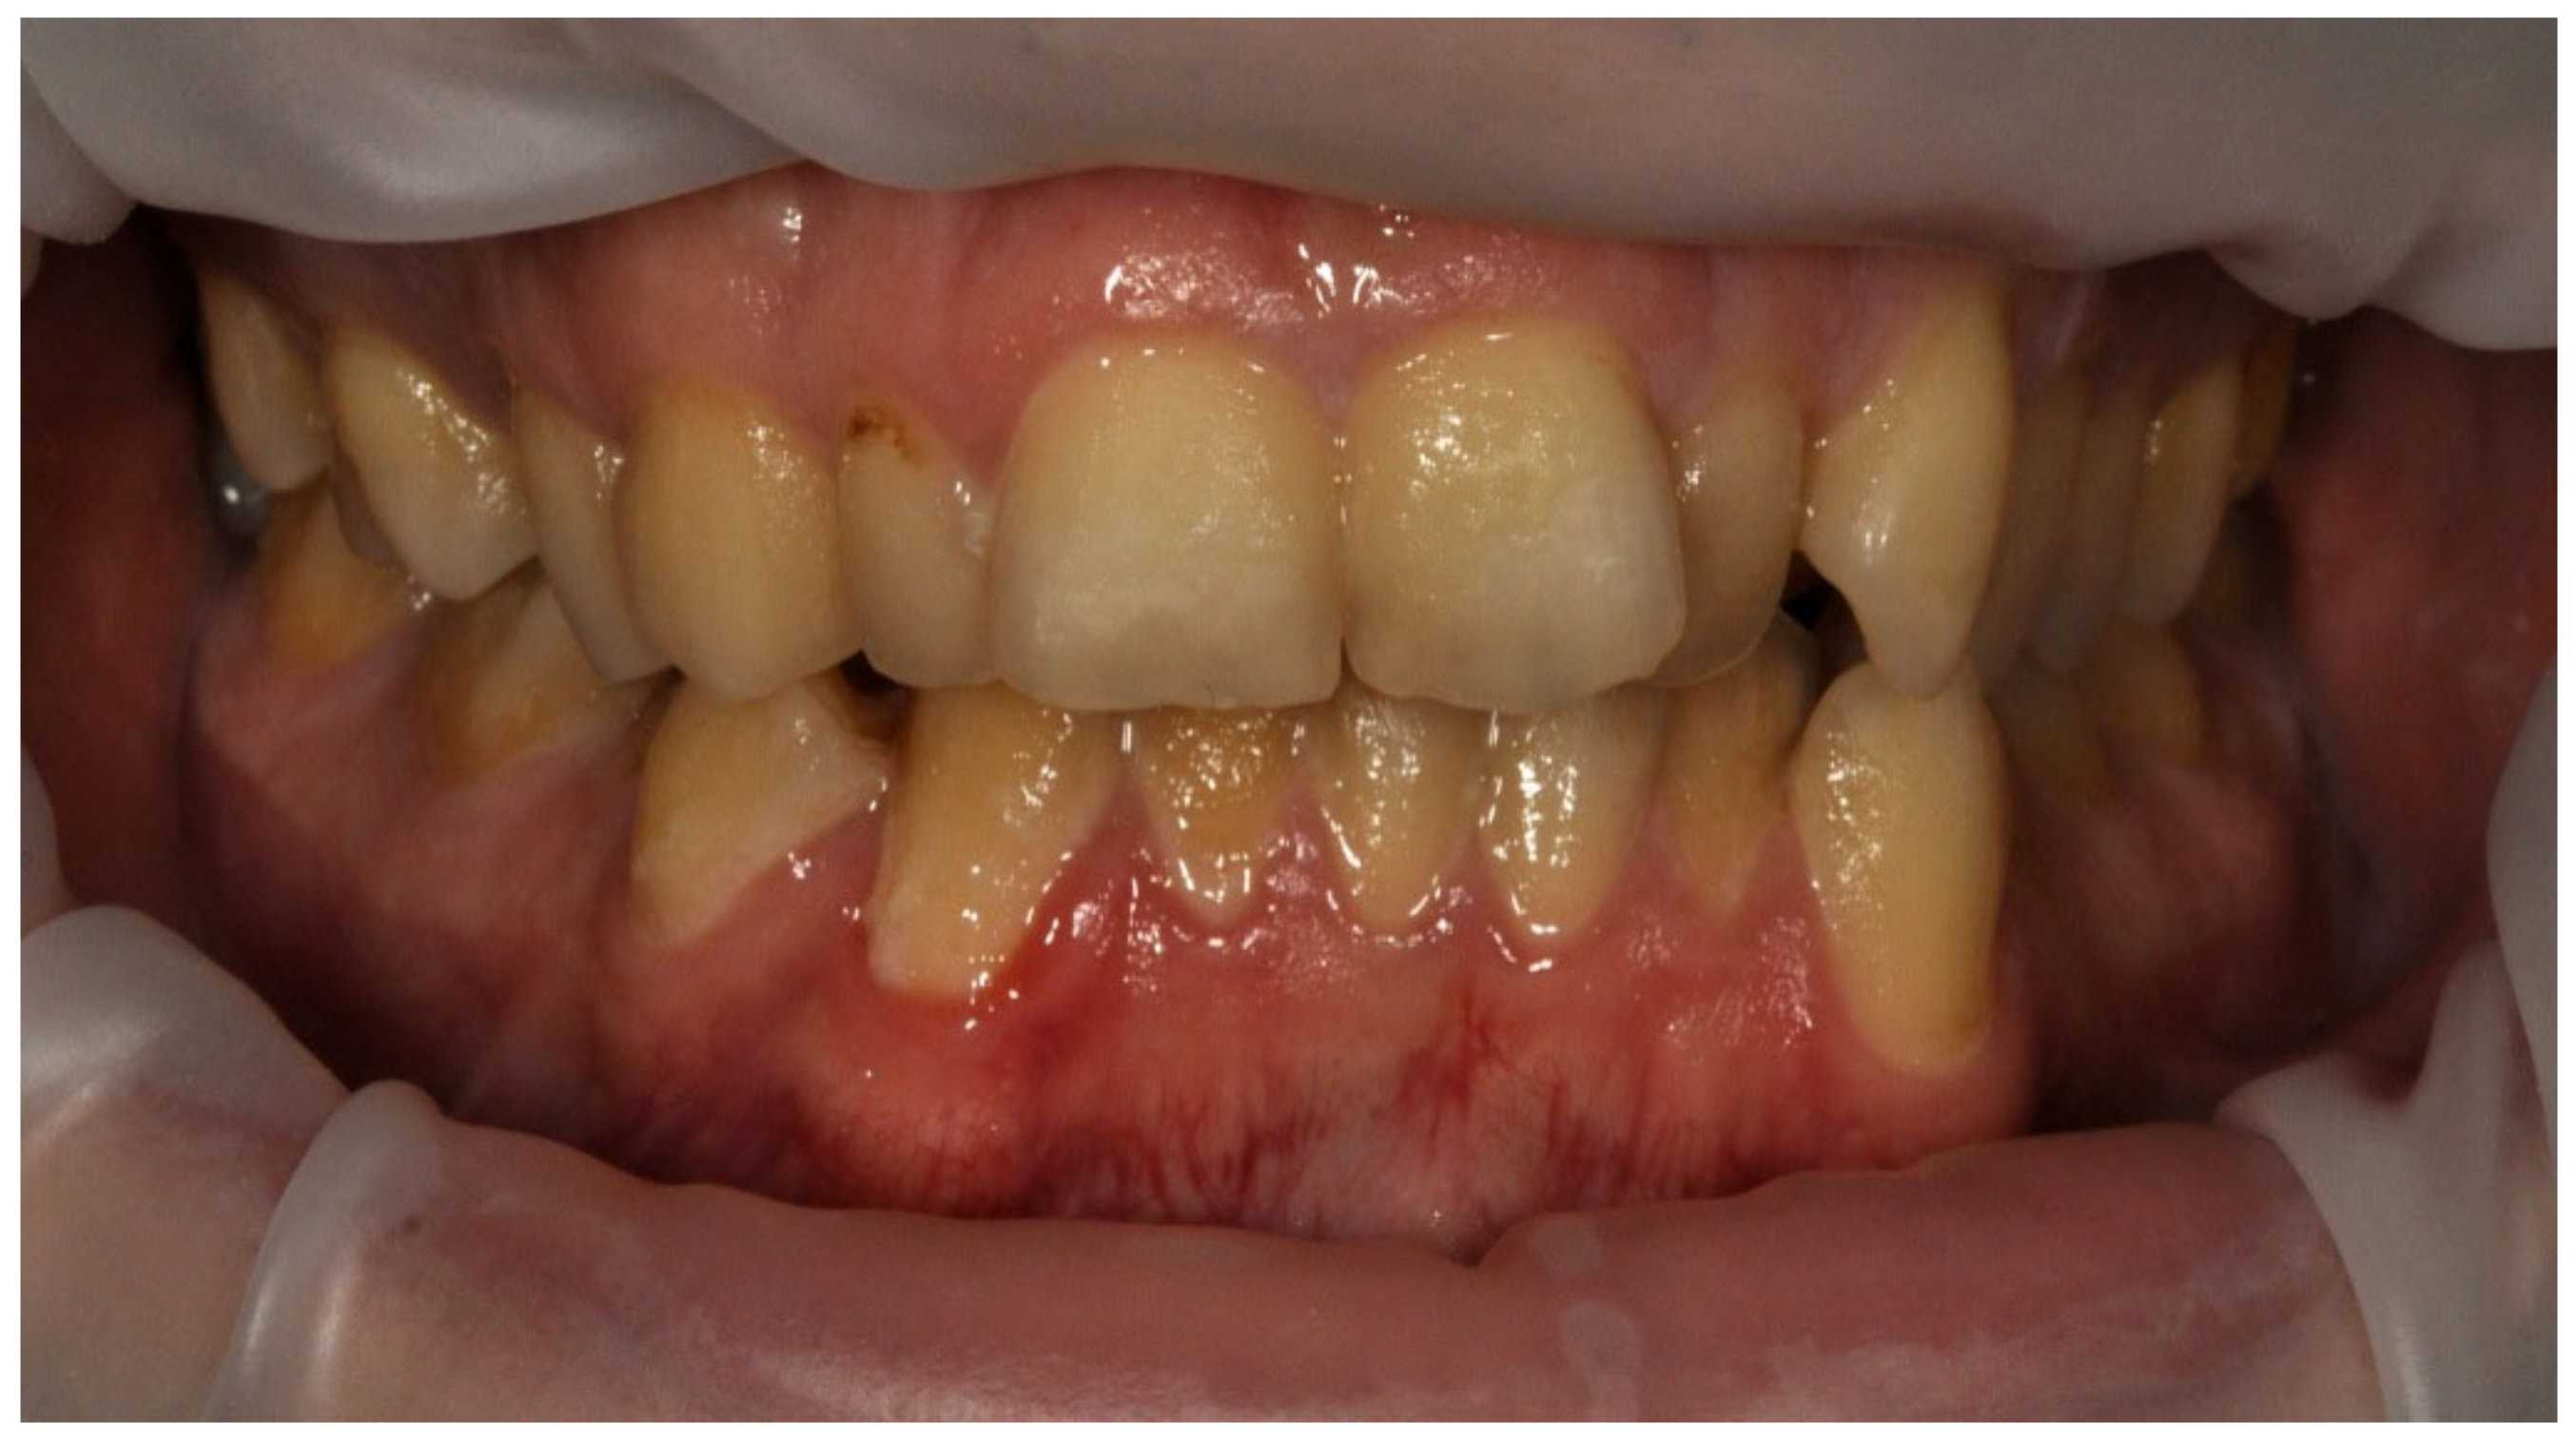

Examples of erosive defects occurring in the examined patients are presented in Figure 6, Figure 7a,b and Figure 8a–c.

Figure 8. (ac) Woman, 29 y.o. Patient with advanced erosion and tooth wear—front view and upper and lower arches.

Ijerph 20 04792 g008